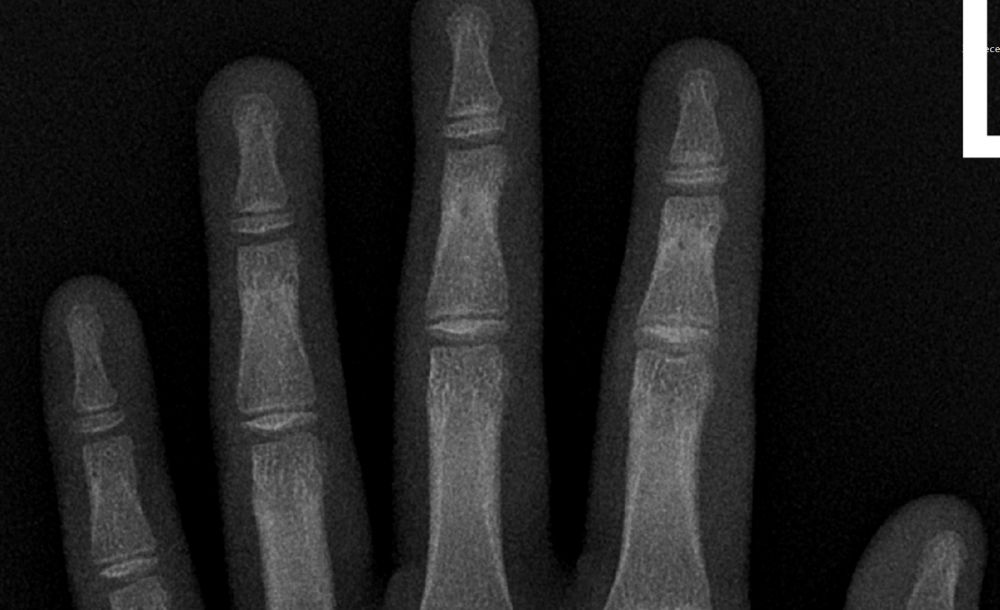

娃哪里都好,就是身高让人发愁。问了医生,医生说不要着急,男孩晚长……

加拿大的医生实在太佛系,但娃马上就要进入青春期了,我再不抓住这最后的长高机会,那就是我这当妈的巨大失败!

为此,我和娃爸吵了好几次。娃爸坚持认为等到16岁,如果娃还是全班最矮,再去看医生测骨龄。而我坚决反对,我说现在就要测!娃爸觉得我在给娃增加身高焦虑,而我[

娃啥都好,就是个子矮,长不胖,真是愁死个人了~~~

要说长身高,首先要靠基因,其次要多吃,多睡,多运动。大家给分析分析,问题到底出在哪里?

娃出生的时候早产,比别的孩子小了10个厘米。

爸妈的身高和新百米飞鱼潘展乐的爸妈身高是一样的,不求娃能长到1米9,但也不要一直是班里最矮的一个吧。。。

娃是游泳队的,运动有点过量。。。每周游5次,每[